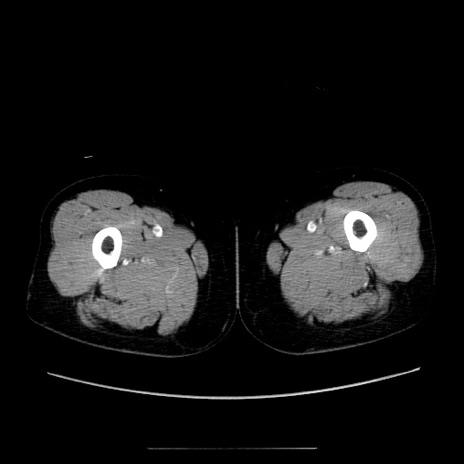

【症例】70歳代女性

【主訴】お腹が張る

【現病歴】1週間くらい前から腹部膨満の自覚あり。昨日夜から増悪したため、本日救急外来受診。

【身体所見】意識清明、BT 36.5℃、BP 165/106mmHg、HR 80bpm、SpO2 98%、腹部:膨満、軟、自発痛・圧痛なし、触診にて不快感あり、腸蠕動音:減弱

【データ】WBC 12600、CRP 1.04